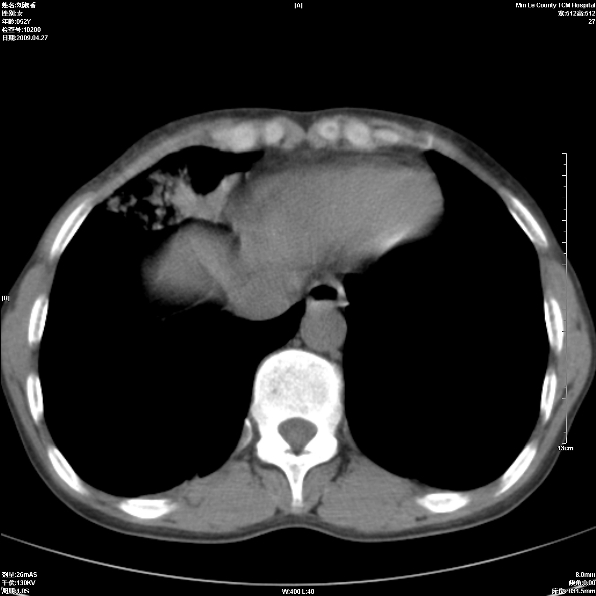

标题: CT19625:女52间断性喀血 [打印本页]

标题: CT19625:女52间断性喀血

病灶内可见含气影。考虑右肺下叶内基底段炎症

考虑右肺中叶感染性病变并右肺中、下叶肺泡积血;建议抗炎、止血治疗后复查。

右肺中叶炎症;右肺中、下叶肺泡积血

右肺中叶支气管扩张并感染或咳血沉积,块右肺中下叶肺泡积血。

右肺中叶慢性炎症伴局部支扩并中下叶肺泡积血。

考虑右肺中叶感染性病变并右肺中、下叶肺泡积血。建议治疗后复查。